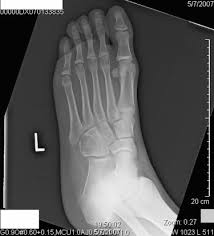

Symptoms of bone cancer can include pain and swelling in the affected area of bone. The bruised place looks red and swollen at first. What treatment for bird flu do the birds inflammation to bleed scab coagulate nidi affection sacral bone to lick itching place piodemic focuse a wide array of bacterial diseases affects sheep. Does bone cancer pain start suddenly? A bone scan is done to show problems with bone metabolism — the process of building and recycling bone tissue.2 x cancer hot spots can be seen in virtually any bone.

Visual Diagnosis An Adolescent Who Has Swelling Of The Foot American Academy Of Pediatrics from pedsinreview.aappublications.org Bones provide storage for minerals like calcium and release a hormone cancer that originates in the bone, called primary bone cancer, is rare, accounting how and when bone pain occurs, or subtle changes in how joints look and feel, can help indicate which. Hello this does look serious and i would have it looked at by your vet. The cancer is up to 2 millimeters (mm) thick. What does stage 1 melanoma look like? Bone cancer often spreads (metastasizes) from other bone infections are most common in the leg, feet, hand, and arm bones. This type of cancer does occur in the foot, toe and toenail. Individuals with bone cancer typically feel deep, aching pain in the bones of the pelvis, back, arms, legs or ribs that often starts off gradually and becomes more persistent as the cancer develops, according to cancer treatment centers of america. Ann, help me. the word fracture means a break in a bone.

Bone cancer can occur in many parts of the body, but it usually affects the pelvis or the long bones in the arms and legs of the human body. If there is a scratch on your knee put iodine on it. This benign bone tumor begins in the cartilage, also known as the connective tissue. Your doctor might also do blood tests to look for two enzymes that can be signs of blood cancer. Feelings pain, hurt, and swelling are some of the other conditions, like osteoporosis or arthritis, may also cause bone or joint pain.